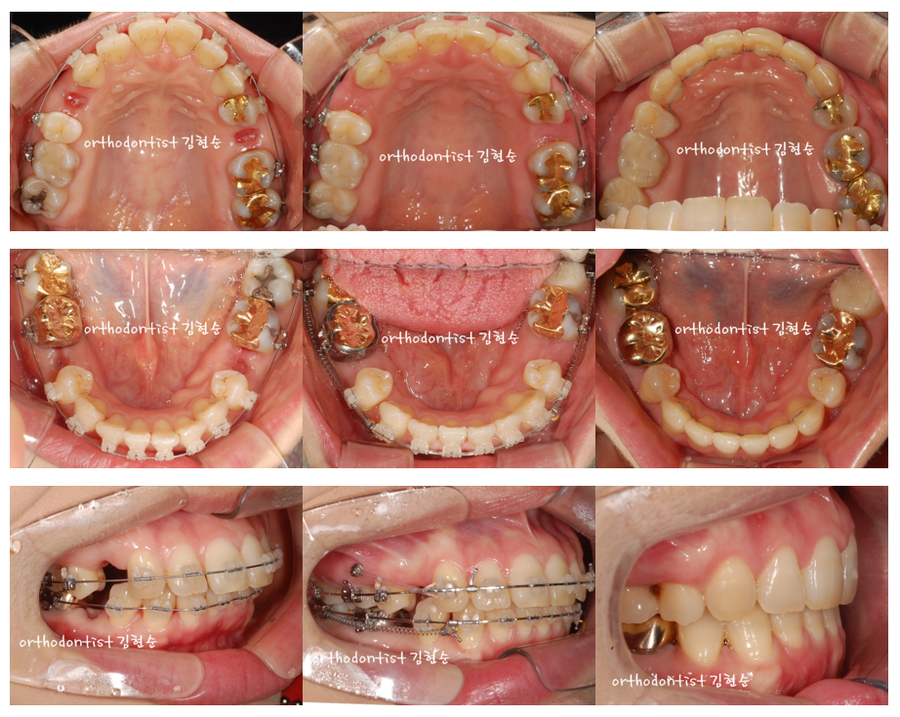

세라믹교정 세라믹치과 돌출입발치교정 증례 10번 자연스러운 미소를 만들어 내는 세라믹치과 교정 증례 입니다. 가지런함은 기본 !! 위/아래 교합을 정밀하게 아름다운 스마일 라인을 만들고 있습니다. treatment 1. 발치 교정 돌출 개선을 위한 발치 교정 14,...

돌출입발치교정 증례 10번

자연스러운 미소를 만들어 내는

세라믹치과 교정 증례 입니다.

가지런함은 기본 !!

위/아래 교합을 정밀하게

아름다운 스마일 라인을 만들고 있습니다.

treatment 1. 발치 교정

돌출 개선을 위한 발치 교정

14, 25, 35, 45 발치

발치 공간으로 치아 배열 후 앞니를 안으로 이동

상악 mini-screw 식립

예상 교정 기간 약 20개월

treatment 2. 비발치 교정

돌출 개선을 위한 비발치 교정

상악 mini-screw 식립하여 모든 치아 후방 이동

치아 사이 삭제

돌출이 확실하게 개선되지 않음

예상 교정 기간 약 10 개월

세라믹 치과 김현순 원장 올림.